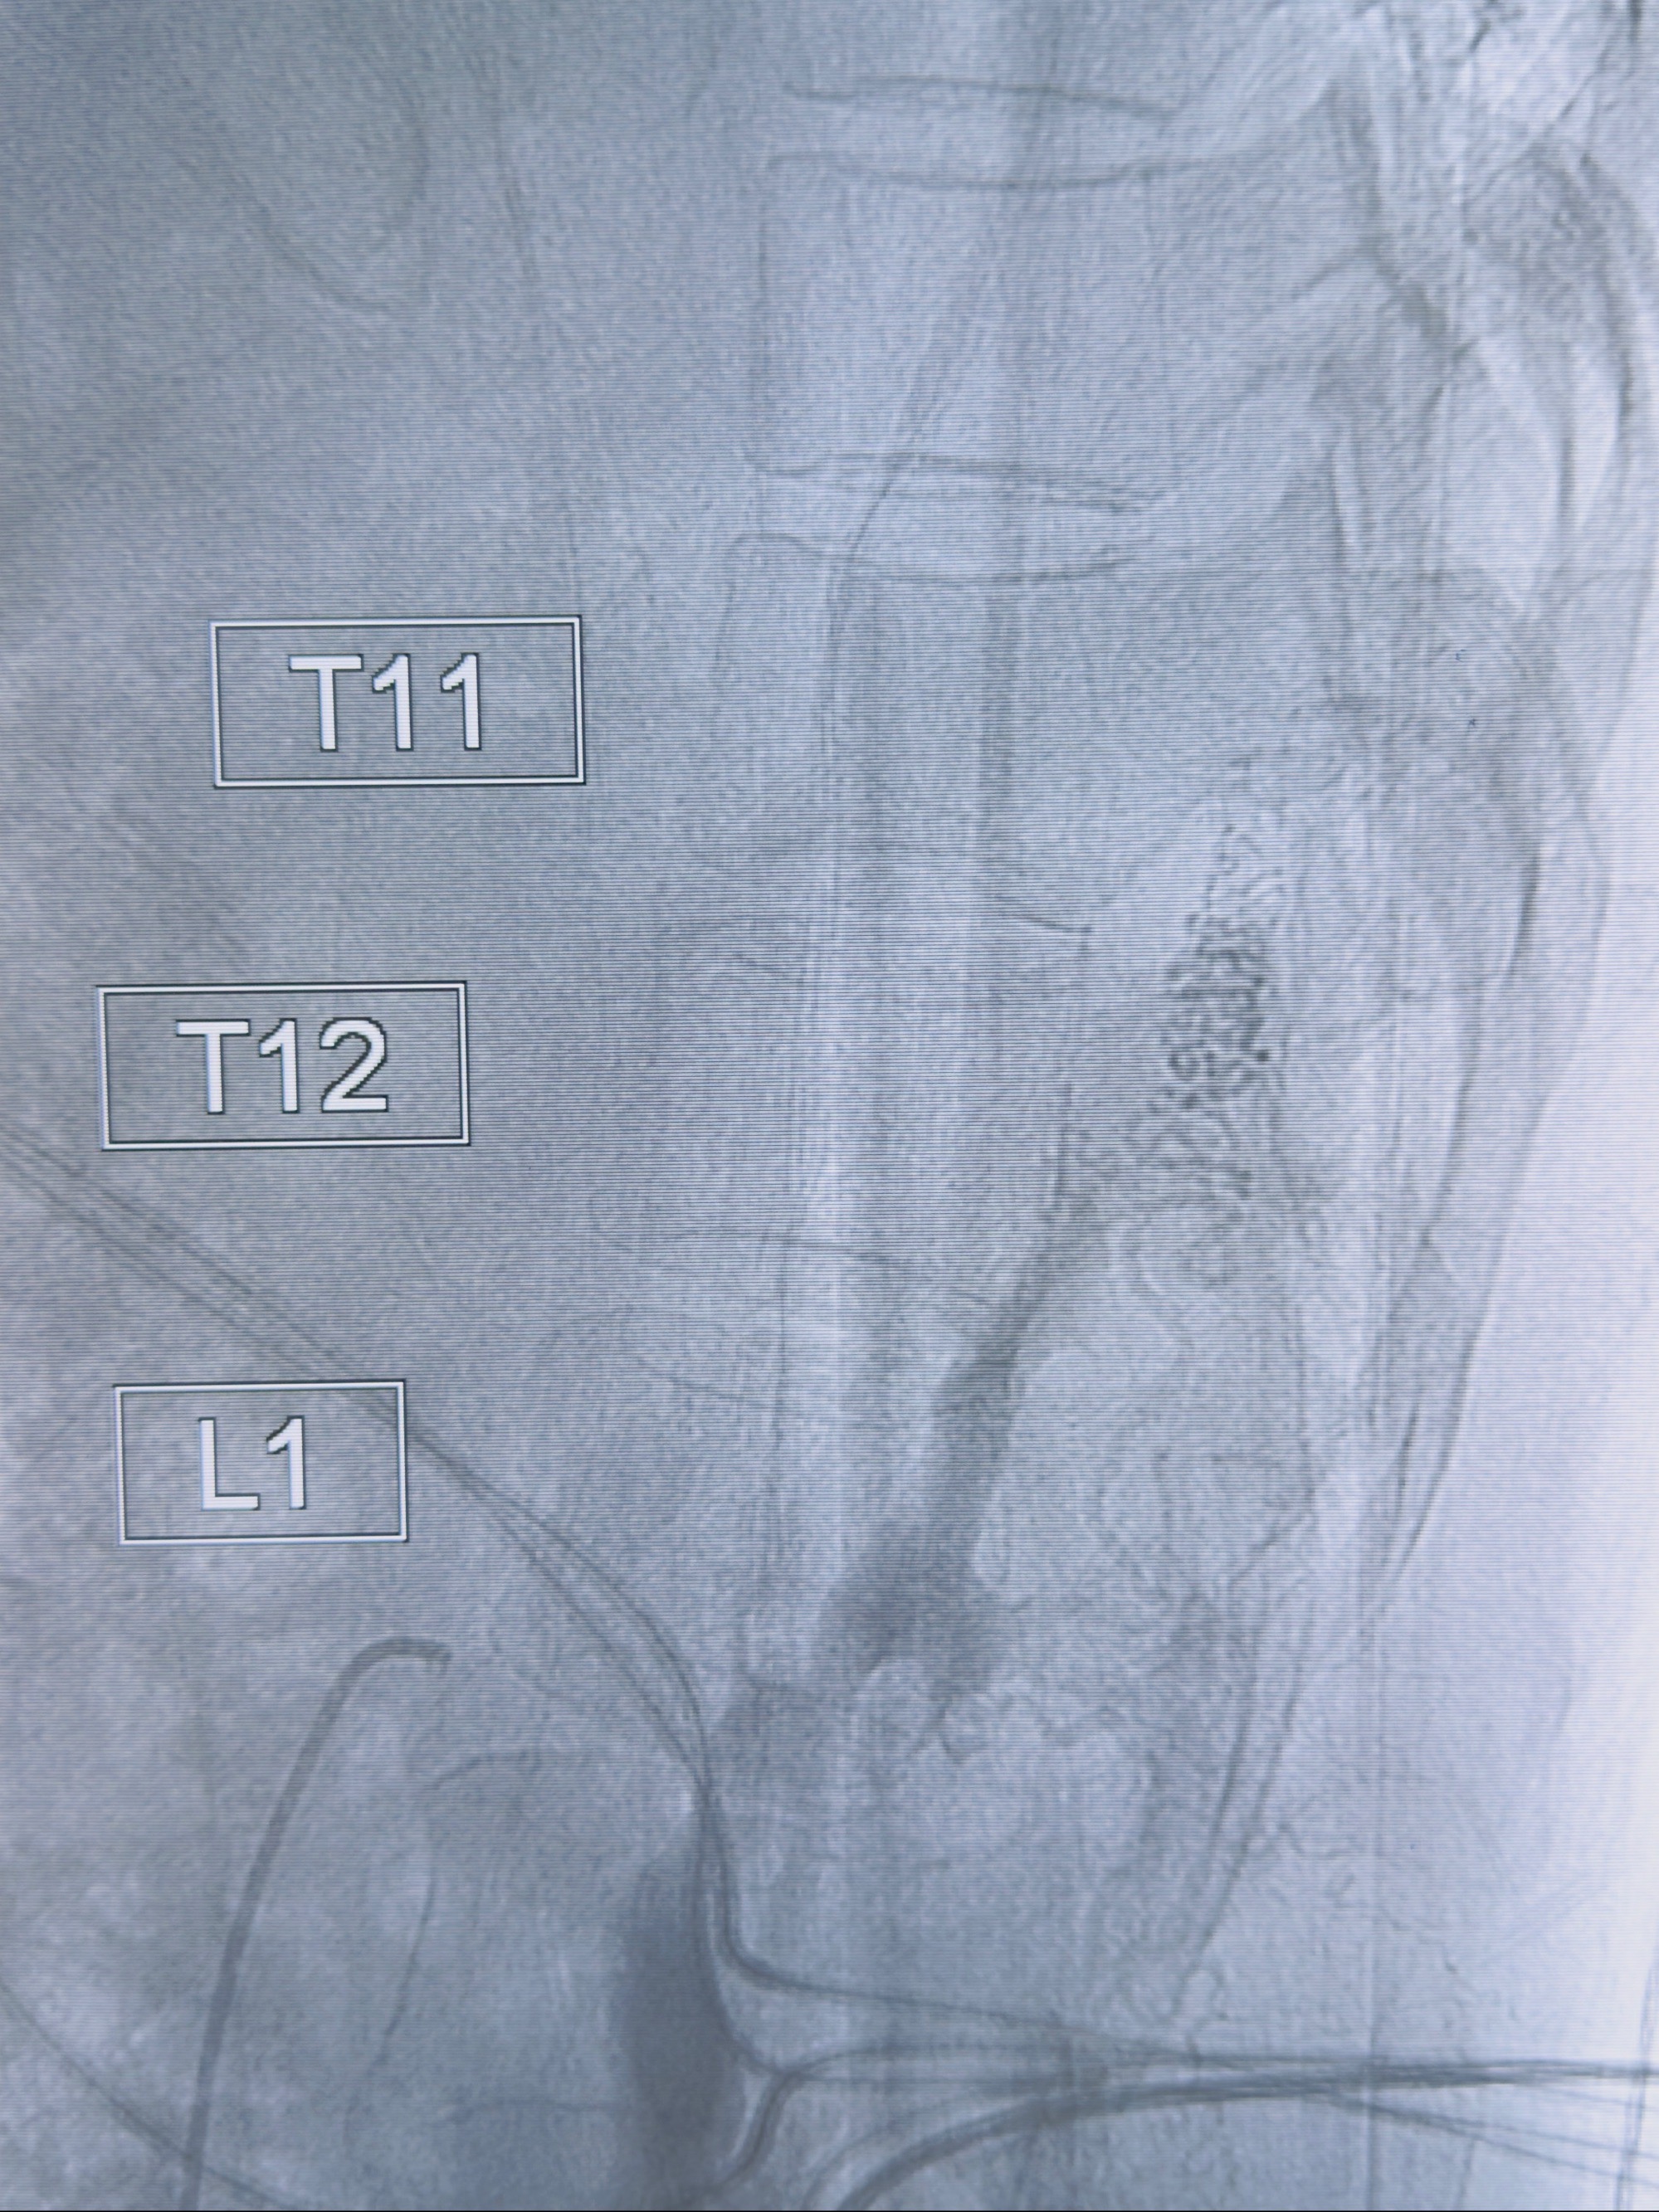

2023-10-13DSA:右侧L1水平硬脊膜动静脉瘘,供血动脉为右侧L1,附近动脉未见明确吻合供血,供血动脉处可见脊髓前动脉发出